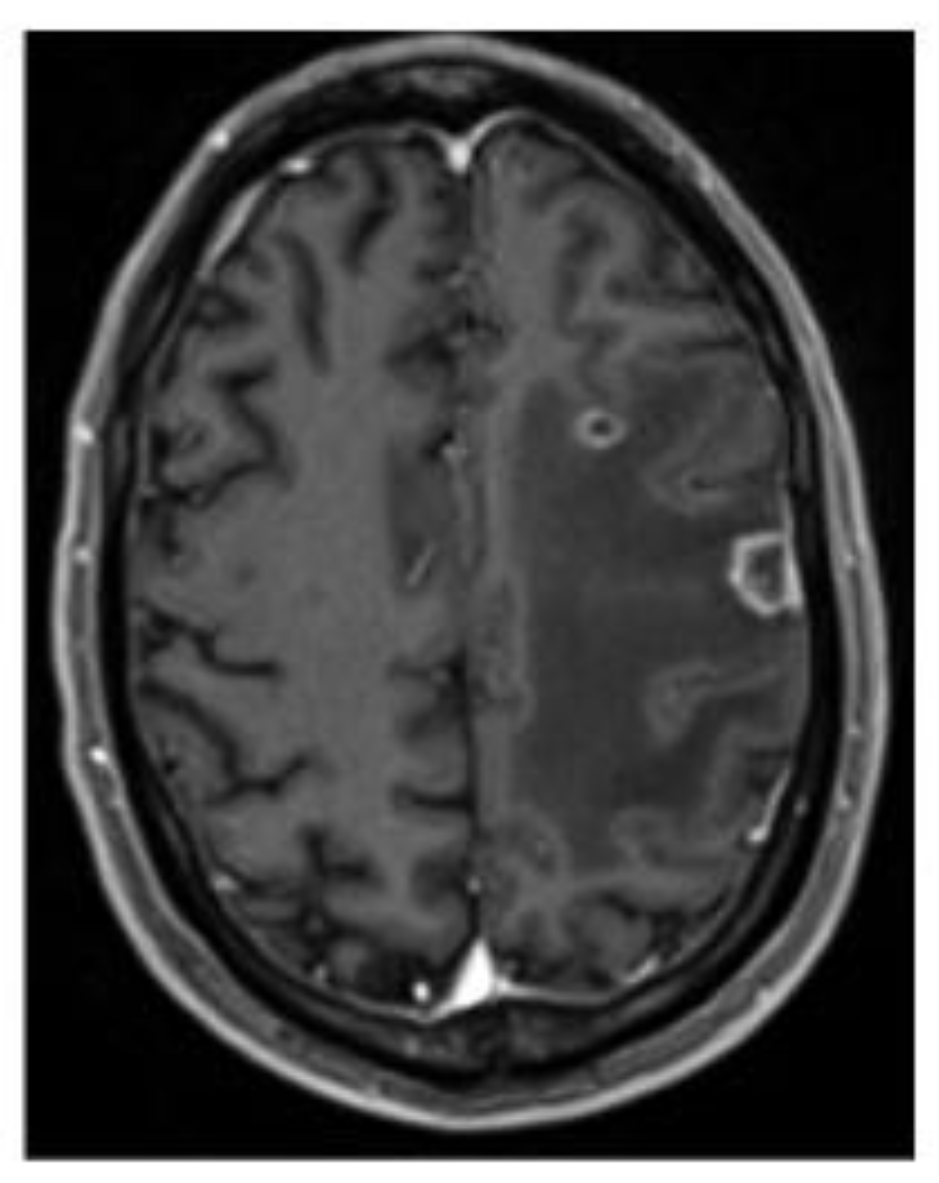

Detection of SARS-CoV-2 RNA by In Situ Hybridization in Lung-Cancer Cells Metastatic to Brain and in Adjacent Brain Parenchyma

2. Case Presentation